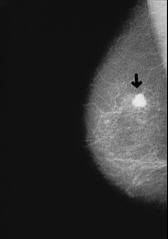

Cancer de mama y muchos otras clases de

cancer: El grupo sanguíneo A es especialmente

propenso para todas clases de cancer similares

al células del grupo A

El organismo del grupo A está propenso a la mayoría de clases de cáncer, quiere decir a todas las clases de cáncer que tienen células similares a células corporales del grupo A.

Ejemplo: Radiografía con cáncer de mama

Caracoles contra cáncer de mama del grupo sanguíneo A

El caracol (Helix pomatia) contiene una lectina con un gran efecto contra las células de cáncer de mama que se comportan de manera similar a las células del cuerpo del grupo sanguíneo A (4 estrategias p.111).

Dr. D'Adamo indica:

<El caracol (Helix pomatia) contiene, como vamos a ver en el capitulo 10 [ver cáncer según grupo sanguíneo] una lectina con un efecto fuerte que coagula células mutadas cancerogenas, y las atrae al tipo A. Se trata de una clase positiva de coagulación porque esa lectina elimina las células enfermas.> (4 estrategias p.111)